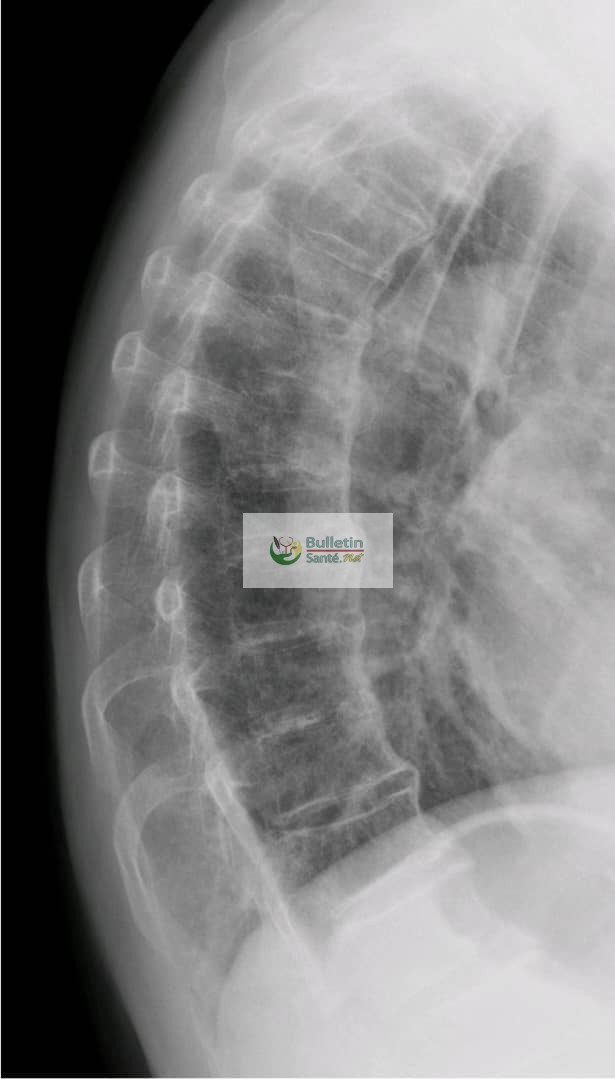

La maladie de Forestier, aussi appelée hyperostose vertébrale, est une affection où les ligaments et les tendons autour des vertèbres deviennent durs et se transforment en os. Cela crée comme des ponts osseux entre les vertèbres de la colonne, ce qui peut rendre le dos raide. Plus fréquente chez les hommes après la cinquantaine que chez les femmes, elle peut toucher le cou, le haut ou le bas du dos.

Comme l’explique le Dr Binta Yaro Savadogo, médecin spécialiste des os et des muscles, la maladie ne donne souvent pas de signe au début. Elle est parfois découverte par hasard lors d’une radiographie. Mais chez certains, elle provoque des douleurs dans le dos et une difficulté à bouger facilement, surtout le matin ou après être resté longtemps sans bouger.